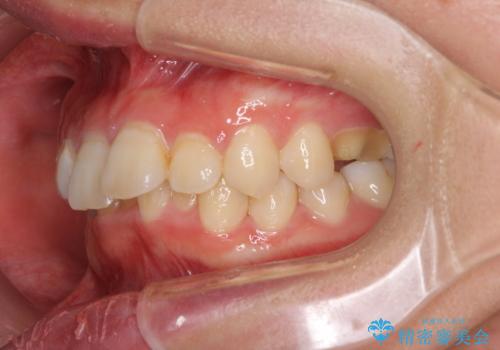

- 矯正装置

- メタルブラケット

- 治療期間

- 1年7ヶ月

- 治療回数

- 10-30回

- 治療費の目安: 120万円(税込)費用は治療当時の料金となります